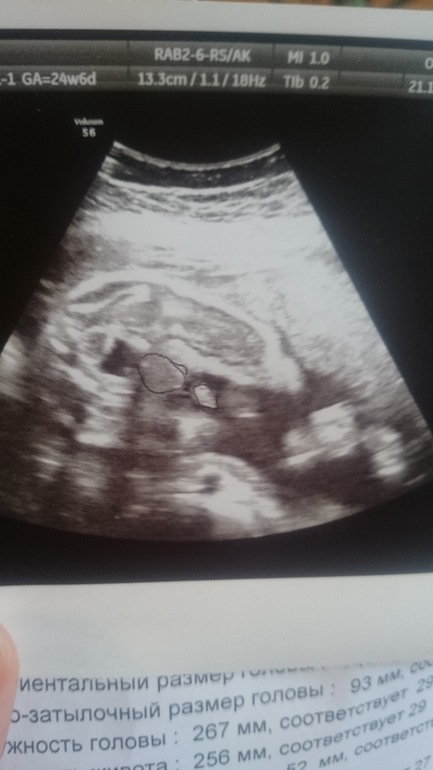

УЗИ в 25 недель

Вопросы про УЗИ, обследования и анализы: что, где, как, когда?Всем добрый день! Вчера сходила на УЗИ, наконец узнала пол,врач сказала мальчик))) смущает то что ставят крупный плод,на 25 неделе соответствует 28 неделям,предполагаем масса 1300!!! У кого детки опережали, подтвердилось ли потом?и фото, кто разбирается, я если честно не очень понимаю, она мне даже ручкой мужские органы обвела))

Поздравляю! Вы не паникуйте. УЗИ тоже немного ошибается. С малышом все в порядке- и это главное! Вижу достоинство мужское))) мне также показали)))